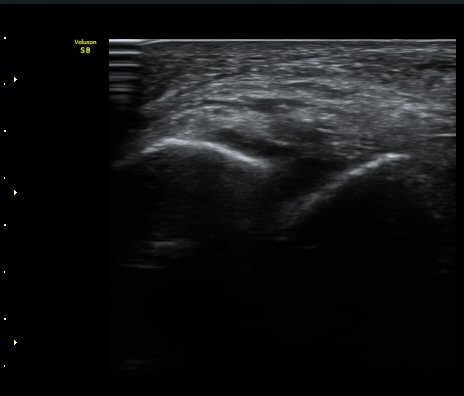

Àüºñ°ñ°æ°ñÀδë Á¾´Ü¸é°Ë»ç¿¡¼­ ƯÀÌ ¼Ò°ßÀ» º¸ÀÌÁö ¾Ê´Â´Ù(±×¸² 2).

±×¸²2) Àüºñ°ñ°æ°ñÀδë Á¾´Ü¸é°Ë»ç±Û